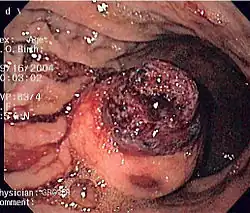

Endoscopic image of GIST in fundus of stomach, seen on retroflexion.

Same GIST seen on forward view of the endoscope showing overlying clot.